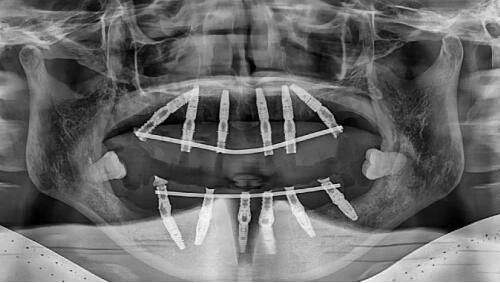

微拉美V提术是一种微创的综合面部除皱提拉紧致手术,是目前全新一代自然生理性微创除皱技术。它突破了传统光电成效不理想、线提升维持时间短、小拉皮面部提升手术创伤大等局限。

1. **双平面提拉技术,多点固定,深层改善轮廓**:采用“双平面提拉”术式,即深提拉与浅雕刻相结合。在脂肪深层和筋膜层中间进行提拉固定,同时利用刺线连接在浅层也起到作用,实现正面饱满度适度、侧面弧度流畅、整体线条收紧上提的三重年轻化成效。从真皮层、脂肪层、SMAS层多点均衡提升,使得提升成效更加稳定持久,维持时间可达3 - 5年。

2. **分段式植入,时间短、效率高**:采用分段式植入技术,每3 - 5分钟即可植入一个小段,整个手术过程仅需30 - 40分钟。与动辄3 - 5小时的传统拉皮手术相比,大大缩短了手术时间,提高了手术效率,同时也降低了手术风险。而且术后即刻就能看到改善成效,让求美者的体验更好。

3. **精微隐蔽切口,修复时间短,自然不留痕**:手术中采用0.3cm的微小切口,切口隐藏在太阳穴两侧的发际线内,术后2天即可修复正常生活,几乎看不到任何手术痕迹。即使在修复期,疤痕也不容易被发现,真正做到了美丽不留痕。

4. **可吸收材料,无需拆线**:使用可吸收的高分子胶原弹力提升带,随着时间的推移,提升带会在体内自然吸收,无需拆线,减轻了求美者的术后护理负担。

5. **提拉更完备,成效更持久**:从多个层面进行均衡提升,成效强而稳定,且不会影响面部表情,术后皮肤真实自然有弹性。术后即可让人年轻8 - 10岁,维持时间在3 - 5年左右,对于追求长期抗衰成效的求美者来说是一个理想的选择。